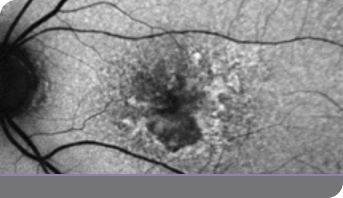

2y 11m

IZERVAY-treated right eye (OD)

Image of right eye treated with IZERVAY and untreated left eye at 2y 11m

Left eye (OS) treated with IZERVAY at 2.5 years

OD=oculus dexter; OS=oculus sinister.

Images courtesy of Dr. Beth Richter.

This is an individual patient case study. It should be interpreted with caution and cannot be considered conclusive. Individual results may vary. In the GATHER trials, sham was used as the comparator.